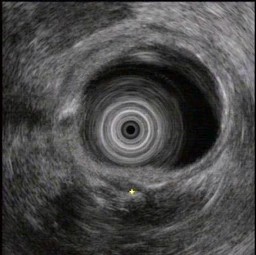

(单选题)胰腺超声内镜如图,最可能的诊断是()。

A:胆管结石

B:急性胰腺炎

C:胰腺癌

D:慢性胰腺炎

E:胰腺囊腺癌